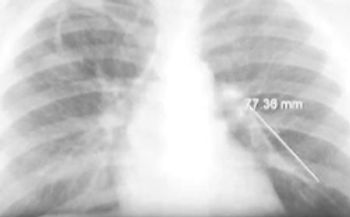

A 50-year-old woman with breast cancer presented for follow-up 2 months after undergoing a left mastectomy and chemotherapy through a port catheter implanted in the right subclavian vein. Because venous access had been difficult to achieve, the catheter was left in situ after treatment.